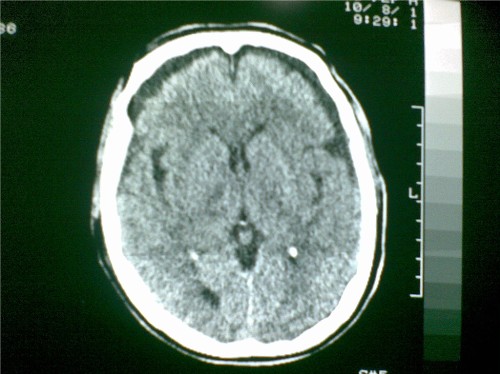

标题: CT28096:男,75岁,外伤10天后,现在恶心、呕吐。是硬膜下积 [打印本页]

标题: CT28096:男,75岁,外伤10天后,现在恶心、呕吐。是硬膜下积

硬膜下积液、右侧基底节、左侧放射冠腔梗。

硬膜下积液、多发性腔梗。

1)双侧额颞顶部硬膜下积液;建议必要时复查。2)多发性腔隙性脑梗塞。